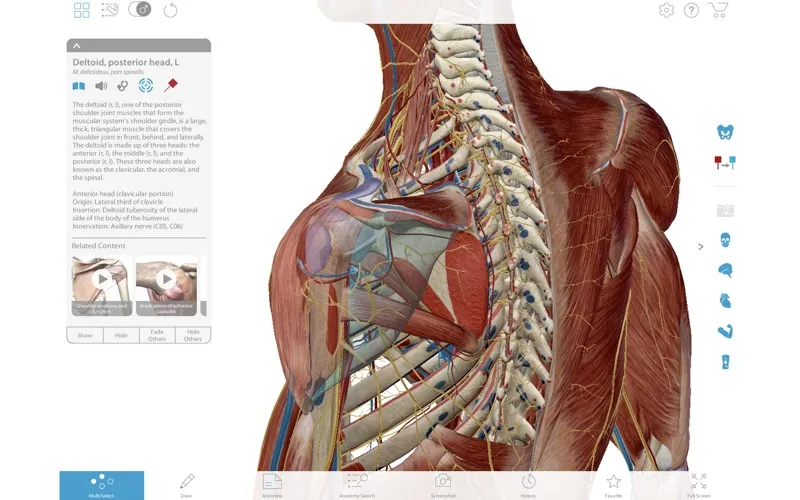

* 💡 Xem chi tiết về chức năng, nguyên ủy, bám tận, cấp máu, và chi phối thần kinh của từng cơ.

* 🔄 Xoay, phóng to, thu nhỏ và “mổ xẻ” các lớp cơ để hiểu rõ hơn về cấu trúc phức tạp.

Người dùng Muscle Premium sẽ có cơ hội được tương tác trực tiếp với mô hình dây chẳng, sợi cơ, xương,… Bên cạnh đó, ứng dụng cung cấp thông tin về các chấn thương liên quan đến cơ xương khớp.